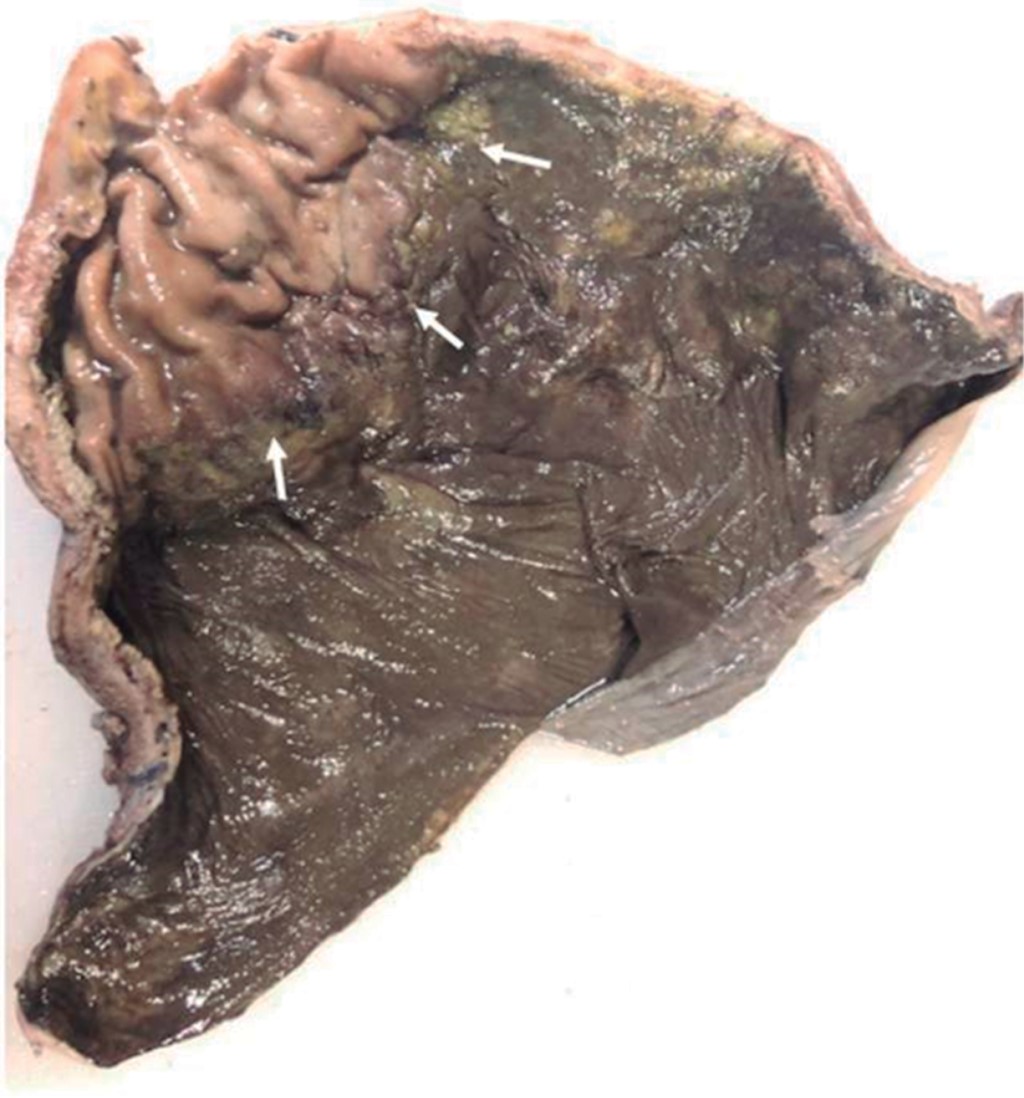

Paciente masculino de 69 años de edad con historia de diabetes mellitus tipo 2 en tratamiento con metformina y clorpropamida, hipertensión arterial en tratamiento con losartán y amlodipino. Se presenta al servicio de urgencias por mostrar cefalea, dolor torácico, tos, mialgias, artralgias y disnea de una semana de evolución. A su ingreso muestra frecuencia cardiaca 114 lpm, frecuencia respiratoria de 24 rpm, saturación de oxígeno de 80% sin apoyo de oxígeno suplementario, glucosa 587 mg/dl, leucocitos de 25,690 cel/mm3, neutrófilos 85%, linfocitos 1.2%, hemoglobina 16.3 g/dl, procalcitonina 3.78 ng/dl, gasometría arterial con pH 7.41, pCO2 21 mmHg, PO2 35 mmHg, HCO3 13 mmol/l, saturación de oxígeno 62%. Se realiza prueba rápida de antígeno para SARS-CoV-2 resultando positiva, tomografía axial computarizada (TAC) de tórax en la que se observan datos radiológicos sugestivos de infección por SARS-CoV-2 (Figura 1), se inicia manejo con oxígeno suplementario, bomba de infusión de insulina, carbapenémicos, antihipertensivos, dexametasona y profilaxis antitrombótica con enoxaparina. A las 48 horas de su ingreso continúa con choque séptico, se inician aminas vasopresoras, se realiza intubación orotraqueal y soporte con ventilación mecánica invasiva, se coloca sonda nasogástrica (SNG), la cual 24 horas posterior a su colocación reporta hematemesis acompañada de distensión abdominal, leucocitosis de 40,000 cel/mm3, se realiza TAC abdominopélvica simple, la cual revela neumatosis gástrica y neumoperitoneo (Figura 2), se efectúa laparotomía exploradora urgente encontrando necrosis de la curvatura mayor del estómago, se lleva a acabo gastrectomía vertical con engrapadora GIA cartuchos morados de 45 y 60 mm (Figura 3), se refuerza línea de grapeo con sutura continua prolene 00, se coloca sonda de yeyunostomía de alimentación a 60 cm del ángulo de Treitz y se dejan drenajes tipo Saratoga. A las 24 horas postoperatorias paciente reporta estabilidad hemodinámica y se suspenden aminas vasopresoras, se inicia nutrición enteral con dieta elemental. El quinto día postquirúrgico muestra adecuada tolerancia a dieta enteral por yeyunostomía, se realiza prueba con azul de metileno por SNG sin evidencia de fugas y descenso de leucocitos a 24,000 cel/mm3. Se recaba resultado de histopatología, el cual revela necrosis panmural asociada a trombosis arterial secundaria a microorganismos compatibles con Mucor sp., por lo que se inicia manejo con anfotericina B (Figuras 4 y 5). En el seguimiento muestra buena evolución, se realiza TAC abdominopélvica con contraste por SNG, la cual descarta fugas y colecciones intraabdominales y se corrobora integridad de la pared gástrica, se retiran drenajes y se da alta de cirugía general el día nueve postquirúrgico continuando manejo a cargo del servicio de medicina interna. Durante los siguientes días de hospitalización, el paciente presenta deterioro cardiovascular y pulmonar, se toma urocultivo, el cual evidencia crecimiento de Candida tropicalis, se realiza TAC de cráneo, tórax y abdominopélvica con contraste oral (Figuras 6 y 7), continúa sin evidencia de fugas a nivel abdominal, se descarta mucormicosis rinocerebral y pulmonar, se reporta probable neumonía bacteriana sobreañadida y neumopatía intersticial secundaria a COVID-19, persiste deterioro clínico y choque refractario, el paciente fallece a 29 días de su ingreso.

Figura 2